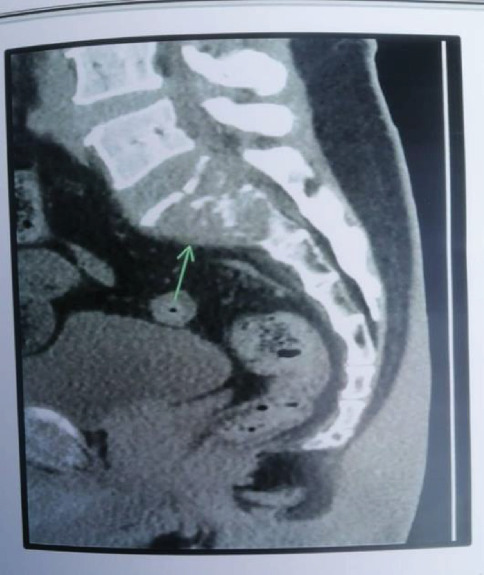

This case report describes a rare occurrence of a single isolated sacral metastasis in a 59-year-old male with clear cell renal cell carcinoma (ccRCC). The patient presented with progressive lower back pain and sacral numbness following a fall. Initial imaging revealed a destructive lytic lesion in the S1-S2 region and a left renal mass. A CT-guided biopsy of the sacral lesion confirmed metastatic ccRCC. PET-CT confirmed no additional metastases. Multidisciplinary management included partial left nephrectomy for the primary renal tumor, stereotactic body radiotherapy (SBRT; 45 Gy/15 fractions) targeting the sacral metastasis, and immunotherapy with sunitinib. The patient experienced significant pain relief within 1-week post radiotherapy and demonstrated stable disease with near-resolution of the sacral lesion at 3-month follow-up. At 12 months, imaging confirmed sustained disease stability. This case highlights the importance of considering metastatic RCC in patients with isolated sacral lesions, even in the absence of disseminated disease, and underscores the efficacy of combining localized ablation, radiotherapy, and targeted systemic therapy. Early diagnosis and a tailored multidisciplinary approach are critical for optimizing outcomes in such rare presentations.

本病例报告描述了一例59岁男性透明细胞肾细胞癌(ccRCC)罕见的单一孤立的骶骨转移。患者在跌倒后出现进行性腰痛和骶部麻木。初步影像学显示S1-S2区破坏性溶解性病变和左肾肿块。ct引导下的骶骨病变活检证实转移性ccRCC。PET-CT证实无其他转移。多学科治疗包括原发性肾肿瘤的左肾部分切除术,针对骶骨转移的立体定向放射治疗(SBRT; 45 Gy/15分数)和舒尼替尼免疫治疗。患者放疗后1周内疼痛明显缓解,3个月随访时病情稳定,骶骨病变接近消退。12个月时,影像学证实疾病持续稳定。该病例强调了在孤立性骶骨病变患者中考虑转移性RCC的重要性,即使在没有弥散性疾病的情况下,也强调了局部消融、放疗和靶向全身治疗联合治疗的有效性。早期诊断和量身定制的多学科方法对于优化此类罕见表现的结果至关重要。